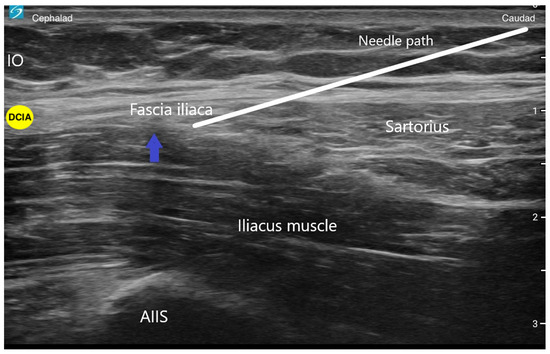

A double-blind randomized control trial demonstrated superior pain relief, less opioid consumption, and less opioid-related sedation when the conventional infra-inguinal fascia iliaca block was compared to standardized systemic morphine analgesia for the management of acute hip fracture pain [10]. A systematic review found the loss-of-resistance-technique fascia iliaca compartment block to be an effective and safe tool for preoperative pain management in patients with hip fractures [11]. With the movement away from landmark-based techniques, an ultrasound-guided technique of the FICB, called a supra-inguinal fascia iliaca block (SIFI), was described and demonstrated to be a more reliable block of the target nerves [12]. This novel approach was created by Hebbard et al. with cadaveric models that showed extensive injectate spread throughout the iliac fossa when using an ultrasound-guided supra-inguinal approach [13]. They describe using a high-frequency probe placed parasagittally over the inguinal ligament close to the ASIS with an in-plane technique and needle entry point 2–4 cm below the inguinal ligament. The needle is advanced through the fascia iliaca at the level of the inguinal ligament, and through hydrodissection, local anesthetic is deposited between the iliacus muscle and the fascia iliaca and superiorly into the iliac fossa, using approximately 30–40 mL (Figure 3) [13]. An important landmark for SIFI is the deep circumflex iliac artery which lies laterally on top of the fascia iliaca. The artery serves as a landmark to confirm adequate local anesthetic spread between the fascia planes. A randomized control trial concluded that for total hip arthroplasty, the supra-inguinal fascia iliaca block provides superior analgesia in the first six hours postoperatively and significantly less morphine consumption in the first 24 h compared to the infra-inguinal approach [14]. Specifically for hip fractures, a retrospective study found the SIFIB group had statistically significantly lower postoperative 24 h opioid consumption compared to the control group, and thus reduced opioid-related respiratory depression after hip fracture surgery in older-old patients (over 80 years old) [15].

Figure 3. This is an ultrasound image of a supra-inguinal fascia iliaca (SIFI) block. The white line represents the direction of the needle. The blue arrow represents the location of local anesthetic injection. IO (internal oblique muscle); AIIS (anterior inferior iliac spine); DCIA (deep circumflex iliac artery).